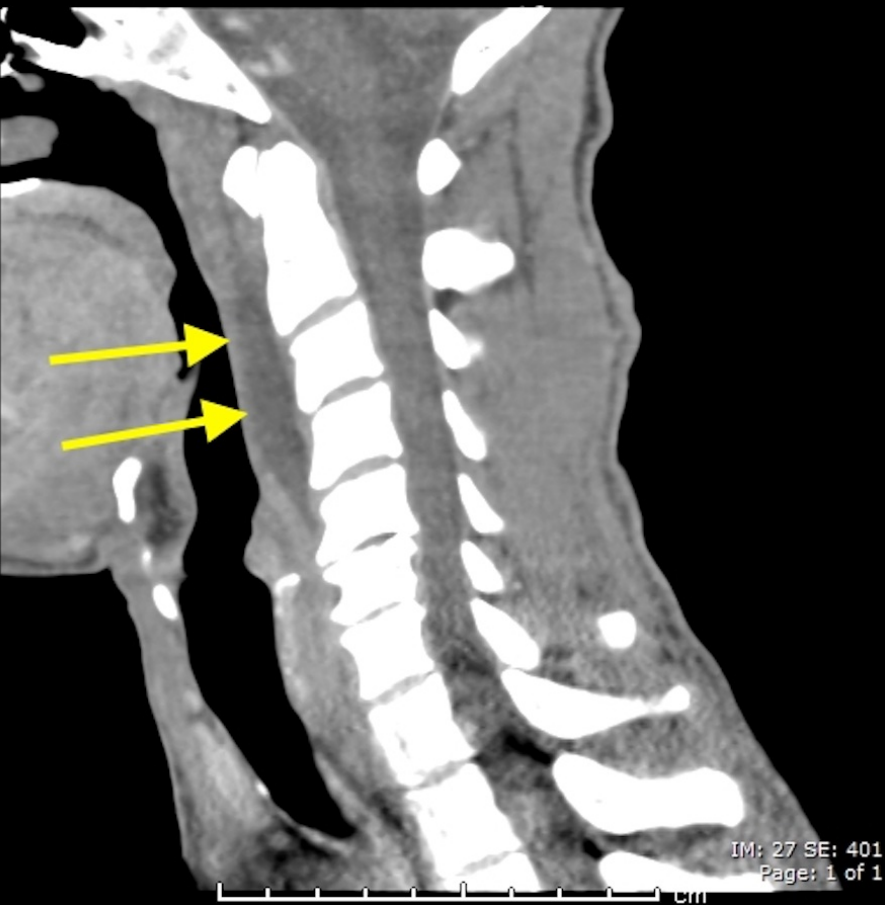

明确诊断主要通过影像学方法,颈椎CT是关键。颈长肌钙化性肌腱炎特异性的影像表现是C1-4椎体前缘软组织肿胀和积液与C1椎体前弓下方不规则钙化沉着共存。

图:C1椎体前弓下方不规则钙化沉着

图:椎前积液

图:椎前积液和C1椎体前弓下方不规则钙化沉着

图:椎前软组织肿胀

颈椎侧位片能够显示上颈椎前纵韧带和颈长肌组成的软组织影增宽,密度增高,正常时宽度为3-4mm,急性炎性水肿时可增宽到1cm以上,并可显示椎前软组织内的钙化影,一般位于C1-2水平。此外,还可见颈肌痉挛引起的颈椎前凸消失。颈椎侧位平片所见的发育性寰椎前弓的下方附属小骨片、寰椎前弓的撕脱骨折以及茎突舌骨肌韧带的钙化极易与本病所见的钙化混淆。

CT的高分辨率能够明确肌腱内的钙化,能够明确是钙化而不是其他骨骼来源的高密度影。钙化一般位于寰椎前弓的下方和枢椎齿状突的前方,少部分可位于下颈椎前侧。CT有助于明确椎体前积液的存在和排除其他病理表现,如骨折或脓肿。MRI对诊断不是必须,但有时可帮助确定软组织异常,排除咽后脓肿,脊椎炎或肿瘤。MRI检查T2加权在椎前可见局限性的裂隙样区域,大多位于C1-4水平,呈高信号改变,这反应是由于炎症引起的积液。T2加权、脂肪抑制序列和T1加权对鉴别积液和脂肪组织、含脂肪的骨髓以及咽后感染、脊椎炎有重要作用。MRI检查在钙化检查方面存在不足,T2加权呈低信号。